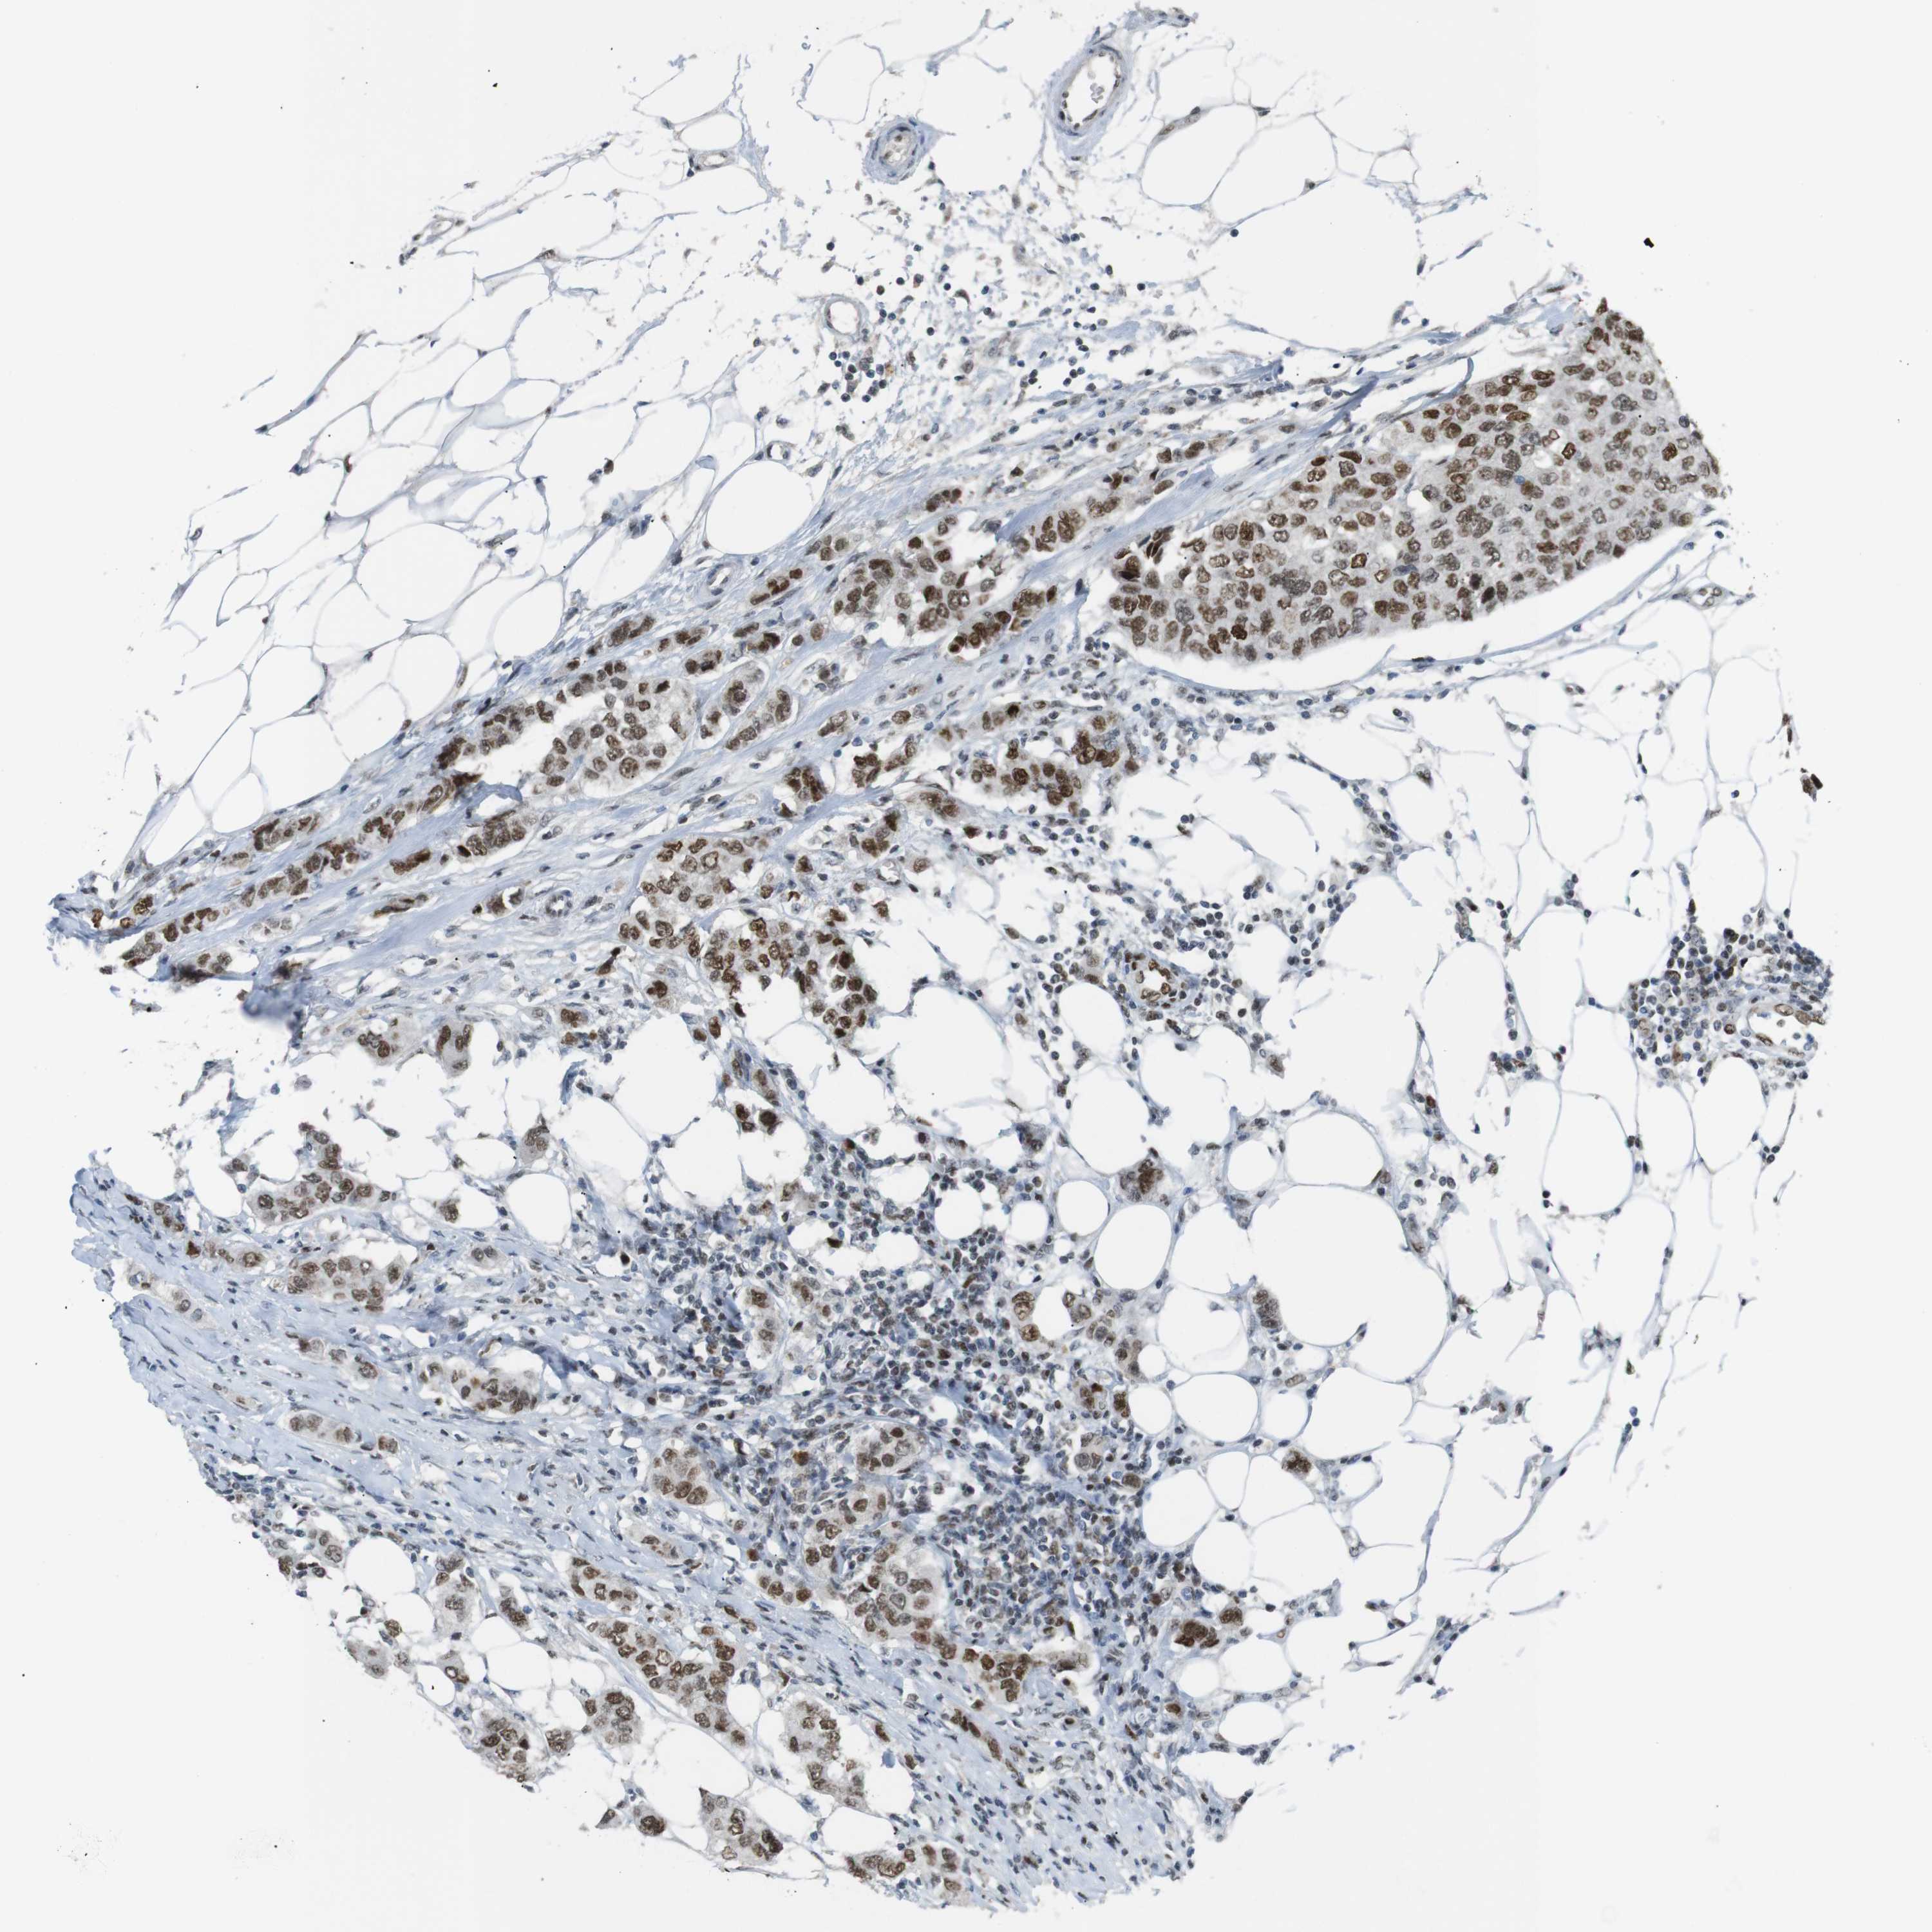

BRCA TCGA BRCA VALIDATION PROTEIN EXPRESSION